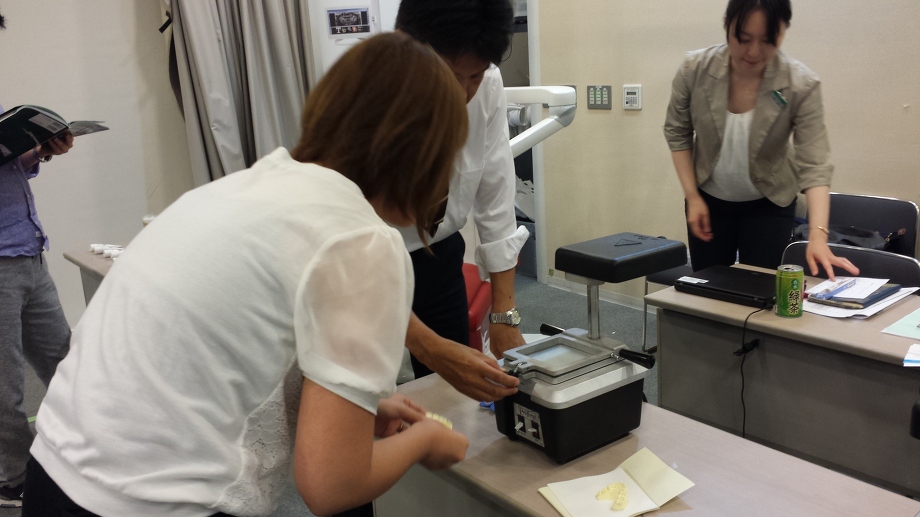

![]() 私たち女性スタッフも、患者様と同じ視点でお話しさせていただけるよう、日々の

私たち女性スタッフも、患者様と同じ視点でお話しさせていただけるよう、日々の![]() 診療のアシストや、歯科や接遇マナーの勉強会

診療のアシストや、歯科や接遇マナーの勉強会![]()

![]() に参加して「わかりやすいことばでの説明」を患者の皆様方にお答えできるように心がけております

に参加して「わかりやすいことばでの説明」を患者の皆様方にお答えできるように心がけております![]()